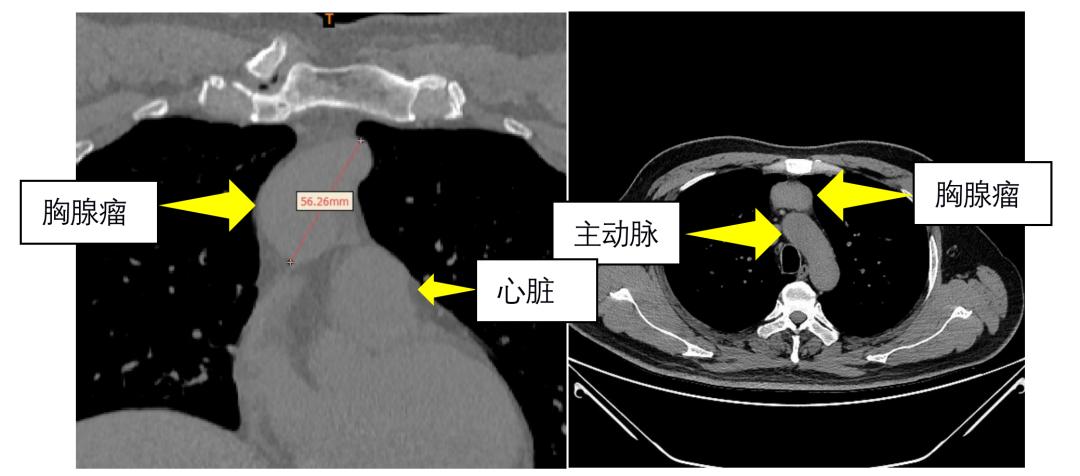

该患者于西安大兴医院体检科常规体检时发现了前纵隔肿瘤,直径约3*6cm,紧邻心脏大血管,影像学检查考虑胸腺瘤可能性较大,患者进一步复查了胸部增强CT,仍然支持胸腺瘤的临床诊断。为此患者来到了西安大兴医院胸外科,经刘同刚主任和王律副主任的团队讨论,决定行剑突下切口胸腔镜胸腺扩大切除术。

手术按照原定计划进行,由于患者瘤体较大,紧临升主动脉、心包和上腔静脉,并有轻度粘连,西安大兴医院胸外科手术团队凭借高超的手术技巧,完整切除了胸腺肿瘤及纵膈脂肪组织,手术后病理提示胸腺瘤B2型。